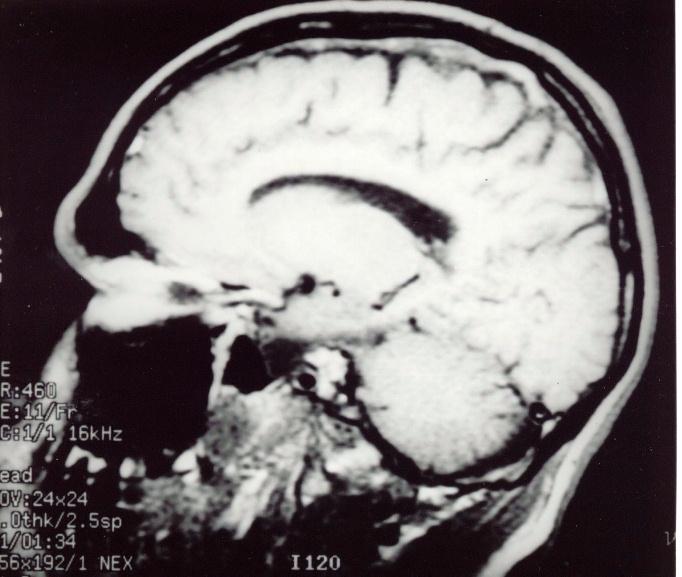

This 58 year-old man complained of a severe headache 12 hours after taking part in the London marathon. He attended the general casualty but no cause was found. He was discharged with a diagnosis of possible migraine. However, the pain persisted and he re-attended the casualty 2 days later. He was found to have bilateral optic disc swellings and an urgent MRI scan was requested. Full blood count revealed high platelet count (thrombocythemia) but otherwise all the other tests were normal.

a. What does the scans show?